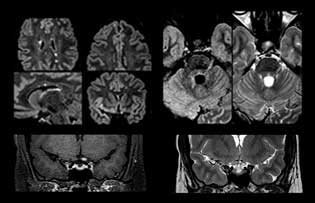

Imaging MS in brain

For MS imaging in the brain, Dr. Savatovsky uses 3D FLAIR as the basic sequence to visualize the lesions and assess the situation and lesion load. “We count the lesions in each location to determine if the criteria of the disease are fulfilled. We use a T2-weighted sequence because our neurologists are used to it. We compare the lesion load on FLAIR with a 3D T1 post-contrast sequence to help us determine whether lesions are old or new. We typically administer the contrast before the patient enters the machine because it shortens the examination time and allows to visualize active lesions that tend to be more visible after several minutes. When a differential diagnosis is difficult, we add sequences such as susceptibility imaging, because some focal MS lesions have a small vein in the center[3].”

MS imaging in spine is more complicated

“For MS imaging in the spine, the basic examination includes a sagittal T2 and a post-contrast sagittal T1-weighted sequence in the whole spine. These are done in two stacks and using thin slices, for example 2 mm, without gap. As in the brain, the T2-weighted sequence visualizes the overall lesion load and helps determine if lesions are old or new. The post-contrast T1- weighted sequence helps in assessing if a lesion is new. We will sometimes add a T1 inversion recovery sequence, which has very good sensitivity, if we don’t find any lesions on T2,” Dr. Savatovsky says. “Additionally, if there is contrast enhancement outside the spine, it’s usually not MS but another kind of inflammation.”